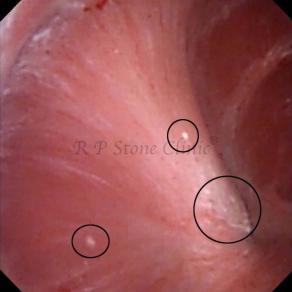

These images are taken as snap shots from the video recording of RIRS Surgery done at our hospital. These are Randall’s Plaques seen with Digital FLEX XC & Digital FLEX XC S. The cream or whitish patches are seen on the tips of RENAL PAPILLAE as seen in images below.

The Below Images Show Small Stones attached to the Renal Papillae.